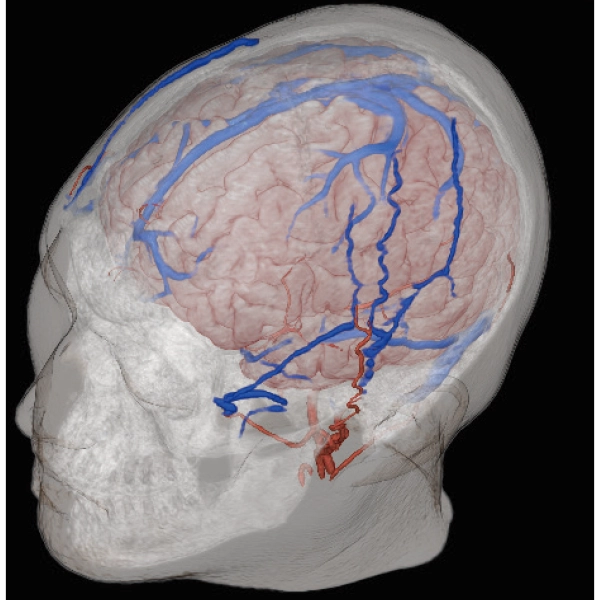

3DTOF MRA (MIP), 1:26

3D Balanced SARGE

with Phase Cycling,

0.93×0.70×1.0(0.5)mm, 1:44

3DTOF MRA RADAR (MIP)